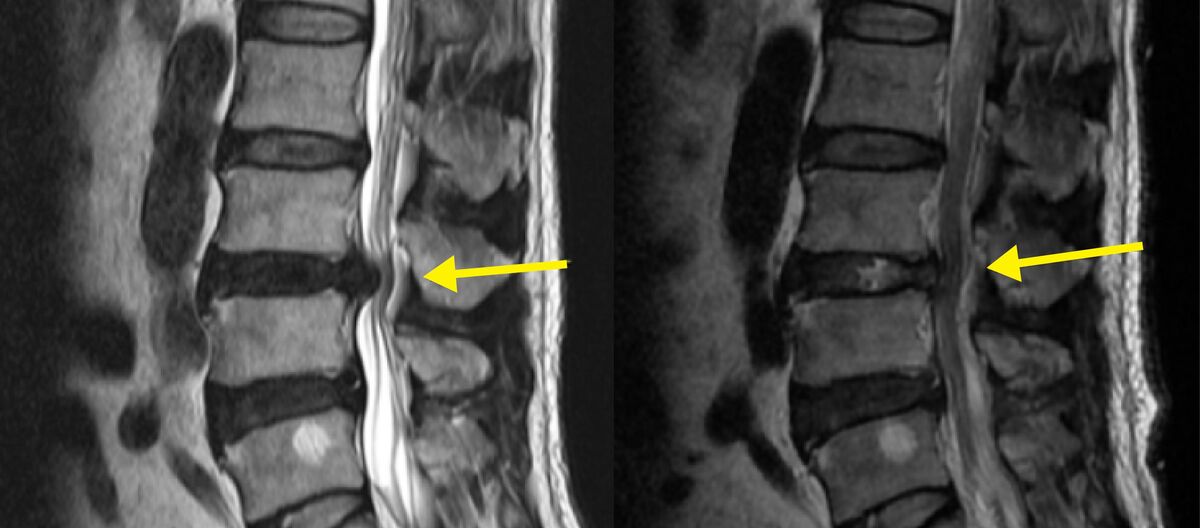

허리디스크는 척추뼈 사이의 추간판이 돌출되어 신경을 압박하는 질환이다. 정상적인 디스크는 충격을 흡수하지만, 잘못된 자세나 과도한 하중이 반복되면 수핵이 섬유륜을 뚫고 나와 신경을 자극한다. 대표적인 증상은 허리통증과 함께 엉덩이, 허벅지, 발끝으로 이어지는 방사통이다. 척추관협착증은 주로 노화로 인한 신경 통로의 협소가 원인이지만, 디스크는 돌출된 수핵이 직접 신경을 압박하기 때문에 통증이 갑작스럽고 전기가 흐르듯 저린 느낌이 동반된다.

하지만 이런 치료에도 통증이 심하거나 근력 저하, 감각 이상, 대소변 장애가 생기면 수술을 고려해야 한다. 대표적인 수술이 최소침습 디스크 제거술이다. 1~2cm 미만 절개로 내시경이나 미세현미경을 통해 병변을 직접 보며 돌출된 디스크 조각만 제거하는 방식이다.